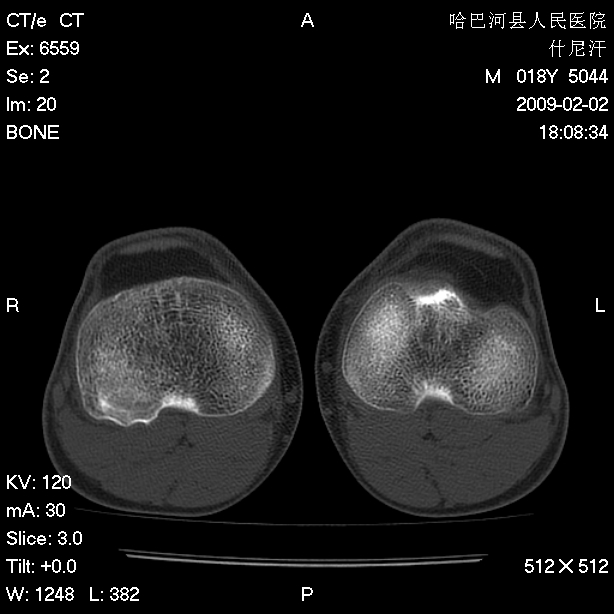

标题: CT17889:外伤后右膝关节反复疼痛3年余 [打印本页]

标题: CT17889:外伤后右膝关节反复疼痛3年余

ct未见明显异常。关节腔未见明显积液,半月板未见明显撕裂。但最好还是mri看看韧带及半月板情况。